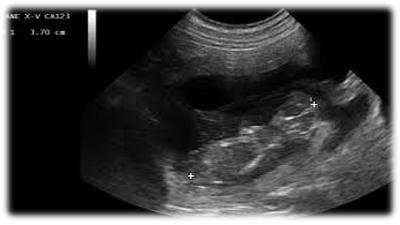

E' un'indagine diagnostica basata sulla risposta di un corpo al passaggio degli ultrasuoni. Gli ultrasuoni partono da una sonda attraversano il corpo e tornano a questa; la macchina, cioè l'ecografo, a questo punto trasforma segnali ricevuti in immagini che vanno dal nero, per un corpo a bassa densità, come un liquido, al bianco per un osso che ha maggior densità. Tra questi due estremi c'è una scala di tonalità di grigi, diversi a seconda dei vari organi. (...)

Da ciò si può capire che non sempre ecograficamente si possono apprezzare delle lesioni, inoltre certe volte alcune di esse hanno lo stesso colore dell'organo sano, quindi l'ecografista non riesce a vederle. Una lesione può quindi essere visualizzata se più bianca, cioè iperecogena, oppure più scura, cioè ipoecogena rispetto al tessuto sano. Per convenzione si parla di tessuto isoecogeno, cioè una tonalità di grigio che sta a metà tra bianco e nero, per la corticale del rene, tutto quello che è più chiaro o più scuro si valuta in confronto a questo e quindi si può stabilire se sano o patologico.

L'ecografia, quindi, presenta dei limiti; è, comunque, una grande metodica di indagine perchè rispecchia esattamente l'anatomia. Con molta probabilità chi non ha dimestichezza specifica vede solo un disegno confuso in bianco e nero, un po' come quei giochi della settimana enigmistica che sono inaccessibili finché non scopri la chiave di lettura, poi diventano evidenti, così l'ecografia quando hai la chiave di lettura diventa più semplice.

No: infatti ci vuole molta esperienza. I colleghi mi aiutano spesso e avendo assimilato la cose basilari, in caso d'emergenza sono in grado di fare alcune valutazioni anche in mia assenza. Ad esempio se arriva un cane investito, possono stabilire se c'è versamento toracico o addominale: infatti il liquido si vede facilmente perchè risulta nero, quindi se la pancia del cane è gonfia e poggiando la sonda si vede la maggior parte dell'immagine nera si può stabilire che c'è un versamento. Certamente per un'ecografia specifica ci vuole esperienza non soltanto nella lettura ma sopratutto nella manualità per cercare le varie strutture.